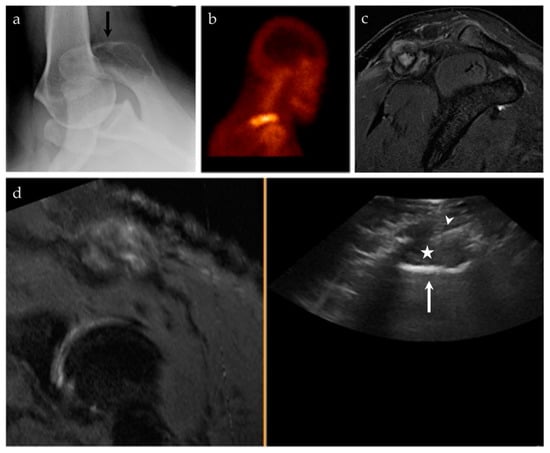

| 17/M | Acromioclavicular joint | US-MRI | Metastatic disease, nasopharyngeal carcinoma | Neoplastic, malignant |

| 18/F | Left posterior knee | US-MRI | Parosteal osteosarcoma, with a chondroblastic component | Neoplastic, malignant |